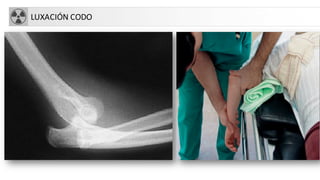

LUXACIÓN CODO

• Más frecuente después de hombro

• Mecanismo indirecto al caer sobre la mano con codo

en extensión

• Valorar paquete vásculo-nervioso